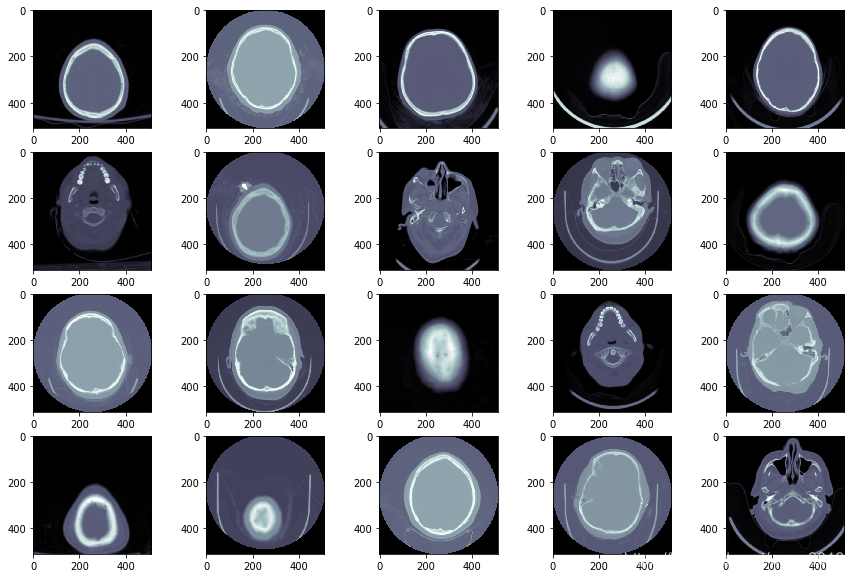

检查图像

医学图像存储在DICOM文件里(*.dcm)。它包括处于文件头的元数据(metadata), 用像素数据表示的原始图像。在Python里,使用pydicom模块访问和操作DICOM文件。首先,将

patientId与DICOM文件匹配。然后,使用pydicom.read_file()方法加载数据。

fig=plt.figure(figsize=(15, 10))

columns = 5; rows = 4

for i in range(1, columns*rows +1):

ds = pydicom.dcmread(train_images_dir + train_images[i])

fig.add_subplot(rows, columns, i)

plt.imshow(ds.pixel_array, cmap=plt.cm.bone)

fig.add_subplot